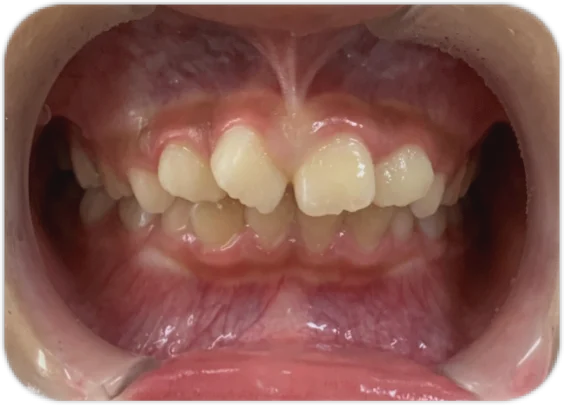

治療後

| 相談内容(主訴) | 前歯のガタガタが気になる |

|---|---|

| 診断結果/行った治療内容 | 叢生/アクティビティ+インビザライン矯正 |

| 治療期間/回数 | 1.5年/18回 |

| 治療費用 | 50万円(マイオブレイス+インビザライン)+アクティビティ 月一5,500円 |

| 治療のリスク/副作用 | 原則の装着時間を守らないと効果が出ません/まれに顎関節に症状が出ることがあります |